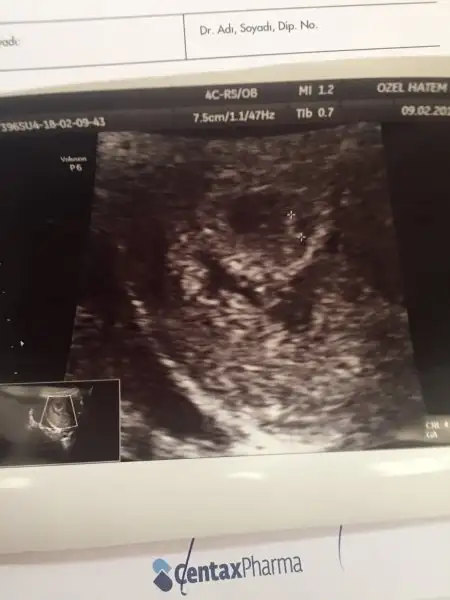

Acilll yardim.7hafta 2 gunlugum.ultraskn resmi yollicam yorumlarsaniz sevinirim.6 haftalikken sagdaydi 7 haftalikken solda..

Ramzi teorisine göre ( bilimsel bir araştırma sonucuymuş ve %85 doğruluğu varmış). İlk 6-8 haftalık ultrason görüntüsüne göre bebeğin kesenin içersinde soldan ya da sağdan girişine göre cinsiyet tahmini yapılıyor. Bilimsel olunca tecrübeli annelerimiz yada anne adaylarımızdan yardım istiyoruz. Doğruluğu var mı öğrenmek adına :) Bizleri aydınlatırsanız çok seviniriz. bu teorieye göre;

Vajinal muayeneyle bakıldıysa eğer;

Sağdan girmiş gözüküyosa aslında solmuş ve ERKEK,

Soldan girmiş gözüküyosa aslında sağmış ve KIZ ,

Karından bakıldıysa eğer,

Soldan girmiş gözüküyosa gerçektede solmuş ve ERKEK,

Sağdan girmiş gözüküyosa gerçekte de sağmış ve KIZ,